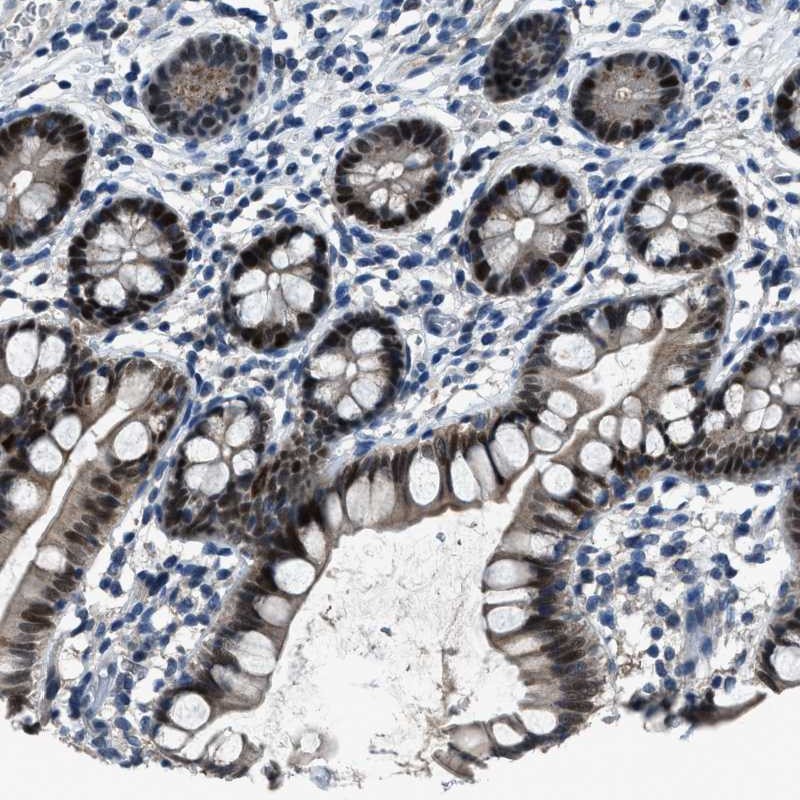

Immunohistochemical staining of human small intestine shows strong nuclear positivity in glandular cells.